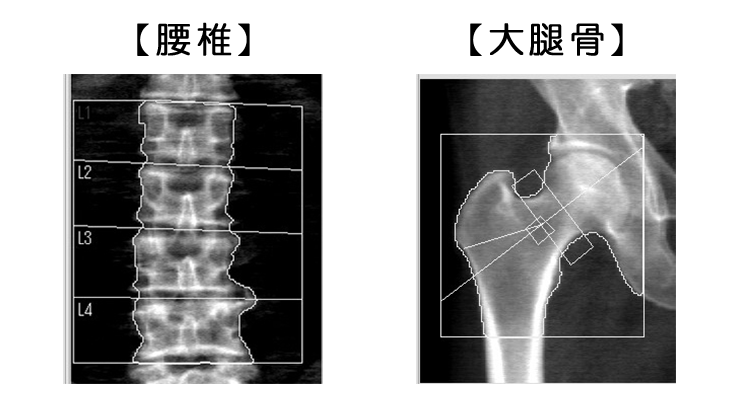

骨塩定量検査

【HOLOGIC社製 Horizon】

骨塩定量検査は、X線を使用して腰椎や大腿骨の骨密度(骨を構成するカルシウムなどのミネラル成分の詰まり具合)を計測する検査で、骨粗しょう症の診断に役立ちます。

当院の装置は、ミネラル成分の詰まり具合だけではなく、TBS insightソフトを用いて「骨質」も同時に調べることができます。骨質を調べることで、骨内の海綿骨の状態を詳しく把握することができます。

下に骨内の海綿骨イメージ図を示します。

海綿骨には骨の柔軟性と強度を維持する役割があり、骨密度が高くても海綿骨のすきまが大きい場合は骨折を起こしやすいことがあります。当院では、海綿骨の状態を加味した最新の骨粗しょう症診断と、骨折リスク評価を行うことができます。